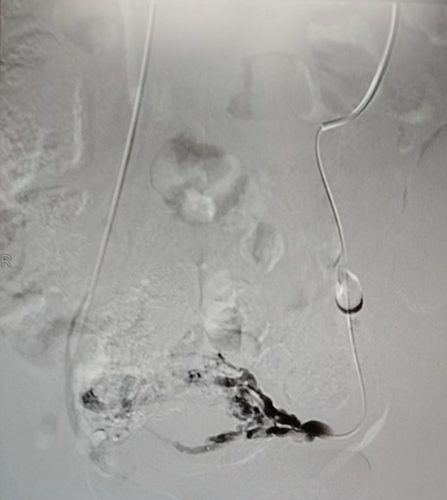

手術(shù)臺上,張濤教授化身“血管工程師”,在局麻下為小雪實(shí)施了“腔靜脈、盆腔靜脈造影 + 盆腔靜脈栓塞術(shù)”。

手術(shù)過程中,靜脈造影就像給血管來了一場 “高清直播”,清晰地展示出左側(cè)卵巢靜脈明顯迂曲增粗,造影劑滯留延遲,盆腔靜脈叢血流瘀滯,左側(cè)卵巢靜脈叢多處病灶更是呈現(xiàn)出團(tuán)狀迂曲增粗、側(cè)枝豐富的“亂象”。

發(fā)現(xiàn) “罪犯血管” 后,張濤教授憑借精準(zhǔn)定位,采用泡沫硬化劑聯(lián)合彈簧圈栓塞術(shù),直接阻斷其血供,徹底切斷“罪犯血管”的“通路”。